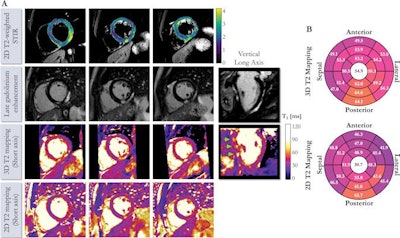

Using the 3D T2 mapping technique, the researchers found that patients with suspected myocarditis had prolonged myocardial T2 values (68 msec ± 7) in comparison with participants without a history of heart disease (51 msec ± 3).

After all T2 map datasets were randomly stored, a cardiologist with 11 years of experience then scored map quality using a four-point scoring system and diagnostic confidence on a three-point system. The cardiologist's map quality scores did not differ significantly between the T2 mapping techniques.

In 21 of the 25 patients, interpretations were the same between the two methods. However, in four (16%) cases, cardiac inflammation was found to be present with high confidence on the 3D T2 mapping images but deemed to be inconclusive on the corresponding 2D T2 mapping images.